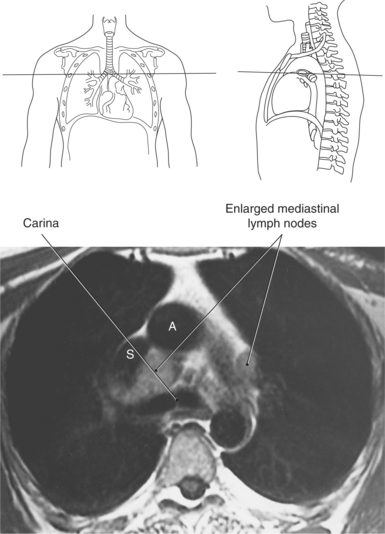

Lymph nodes in the mediastinum are generally clustered around the great vessels, esophagus, bronchi, and carina. Mediastinal lymph nodes are classified according to their location and are grouped into 14 regional nodal stations for use in lung cancer staging (Figure 6.29 and Table 6.2). Lymph vessels and nodes can be difficult to visualize in cross section unless they are enlarged as a result of an abnormality (Figures 6.30 and 6.31).

Key: AO, aorta; PA, pulmonary artery; Inf. pulm. ligt., inferior pulmonary ligament; Phrenic n., phrenic nerve; S, superior vena cava; A, aorta.